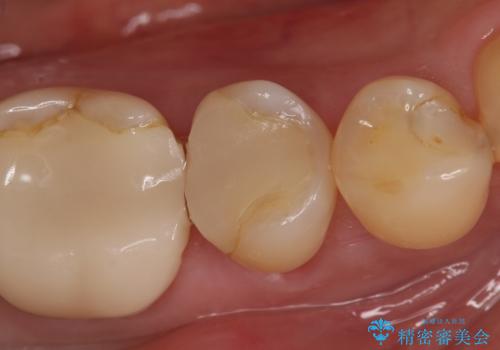

- 右下でものを咬むと痛むので診て欲しいといらっしゃった方の症例です。

検査の結果右下5番目の歯の神経が死んでいたため、根管治療を行った後、オールセラミッククラウンによる補綴を行いました。